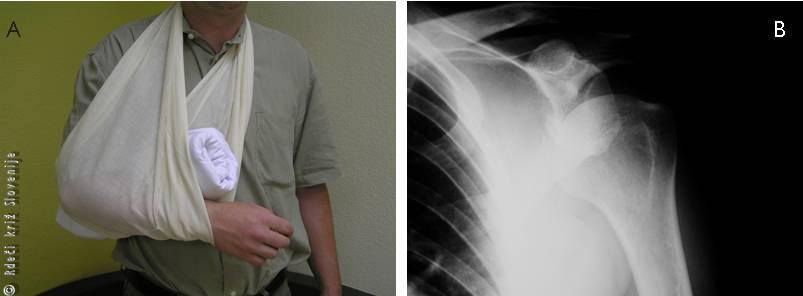

Slika 16

A – Pravilna imobilizacija pri izpahu rame.

B – RTG slika ob izpahu potrdi postavljeno diagnozo in izključi morebitni zlom.